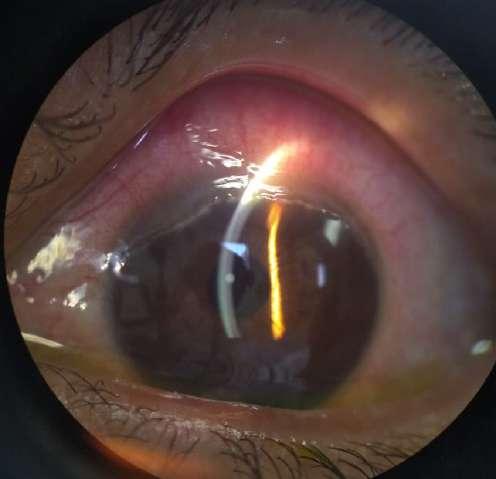

Imágenes aportadas por Dr. Nathan Dukes

ü Imagen A, B y C muestran Subluxación del lente intraocular en paciente con pseudoexfoliación. Sin antecedentes de trauma previo.

ü El síndrome de pseudoexfoliación es un desorden de la matriz extracelular, relacionado con la edad, caracterizado por la producción y depósito de un material brilar en varios tejidos intraoculares y extraoculares.

ü Puede ser unilateral o bilateral y es un factor de riesgo mayor para desarrollar glaucoma secundario de ángulo abierto.

ü Consotuye la causa idenocable más común de glaucoma en el mundo y la causa más frecuente de glaucoma unilateral.

10.B. SUBLUXACIÓN DE LENTE INTRAOCULAR EN PACIENTE CON SD. DE

PSEUDOEXFOLIACIÓN

B C Spinel JE, Alonso MP. Sindrome de pseudoexfoliación

la unidad nacional de o almología. Ciudad de Guatemala. Estudio transversal. Rev SCO. 2018; 51(1): 37-45

A

en la clínica de glaucoma de